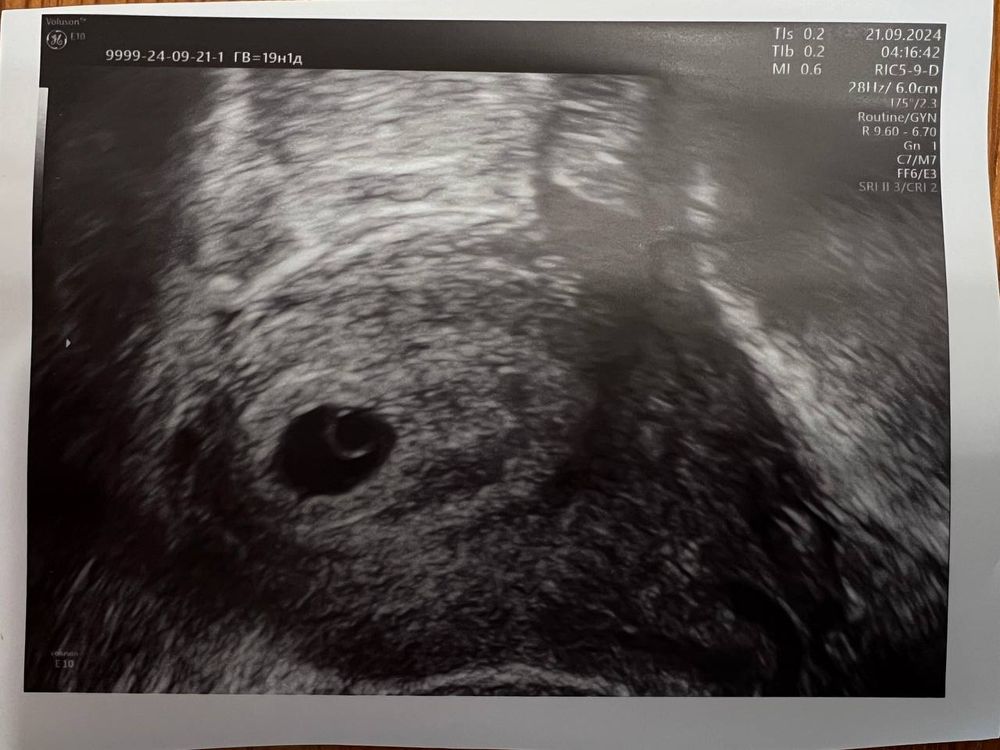

Результаты УЗИИтак, вчера сходила на первое узи на 19дпп, ХГЧ на 18дпп был 5552

ПЯ в верхней трети (я так понимаю это хорошо, перенос был именно туда со средой ЭмбриоГлю) , ПЯ 15,2*12,6 (как считать СВД?), ЖМ 3мм, эмбрион четко не виден - хотя бриллиантовое колечко почти проглядывается)

ПМ были 16.08, О 28.08 , перенос 02.09, по приложению срок 5н3д, врач написала срок 5н ровно на 21.09